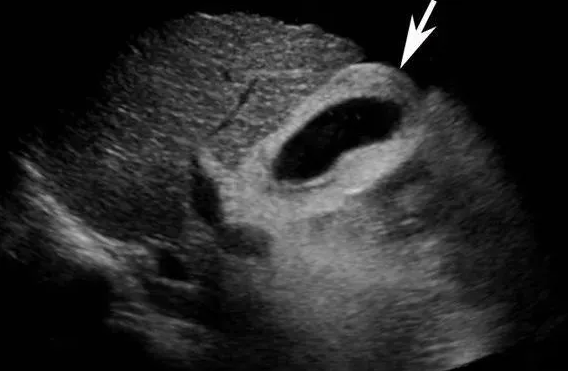

图3,非典型胆囊壁厚。

一般是低蛋白血症患者。其中尤以肝硬化腹水者表现得更为显著,胆囊壁因水肿而弥漫增厚。急性肝炎、右心衰竭、肾脏疾病、多发性骨髓瘤亦可见胆囊壁增厚。